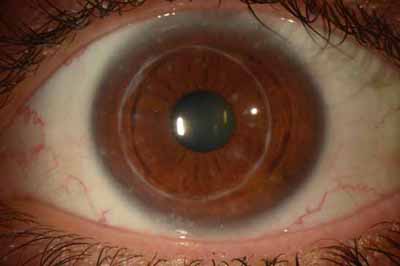

Aspecto Clínico

- Superficie corneal irregular y grisacea

- Opacidades granulares en parche

- Formación de lineas epiteliales elevadas de aspecto granular, que pueden dar imágen de seudodendritas

- Opacidades superficiales satélites

- Ulceración epitelial variante

- Formación de anillo inmunológico

- Dolor intenso (no siempre presente)

Superficie corneal irregular y grisácea

Opacidades granulares en parche